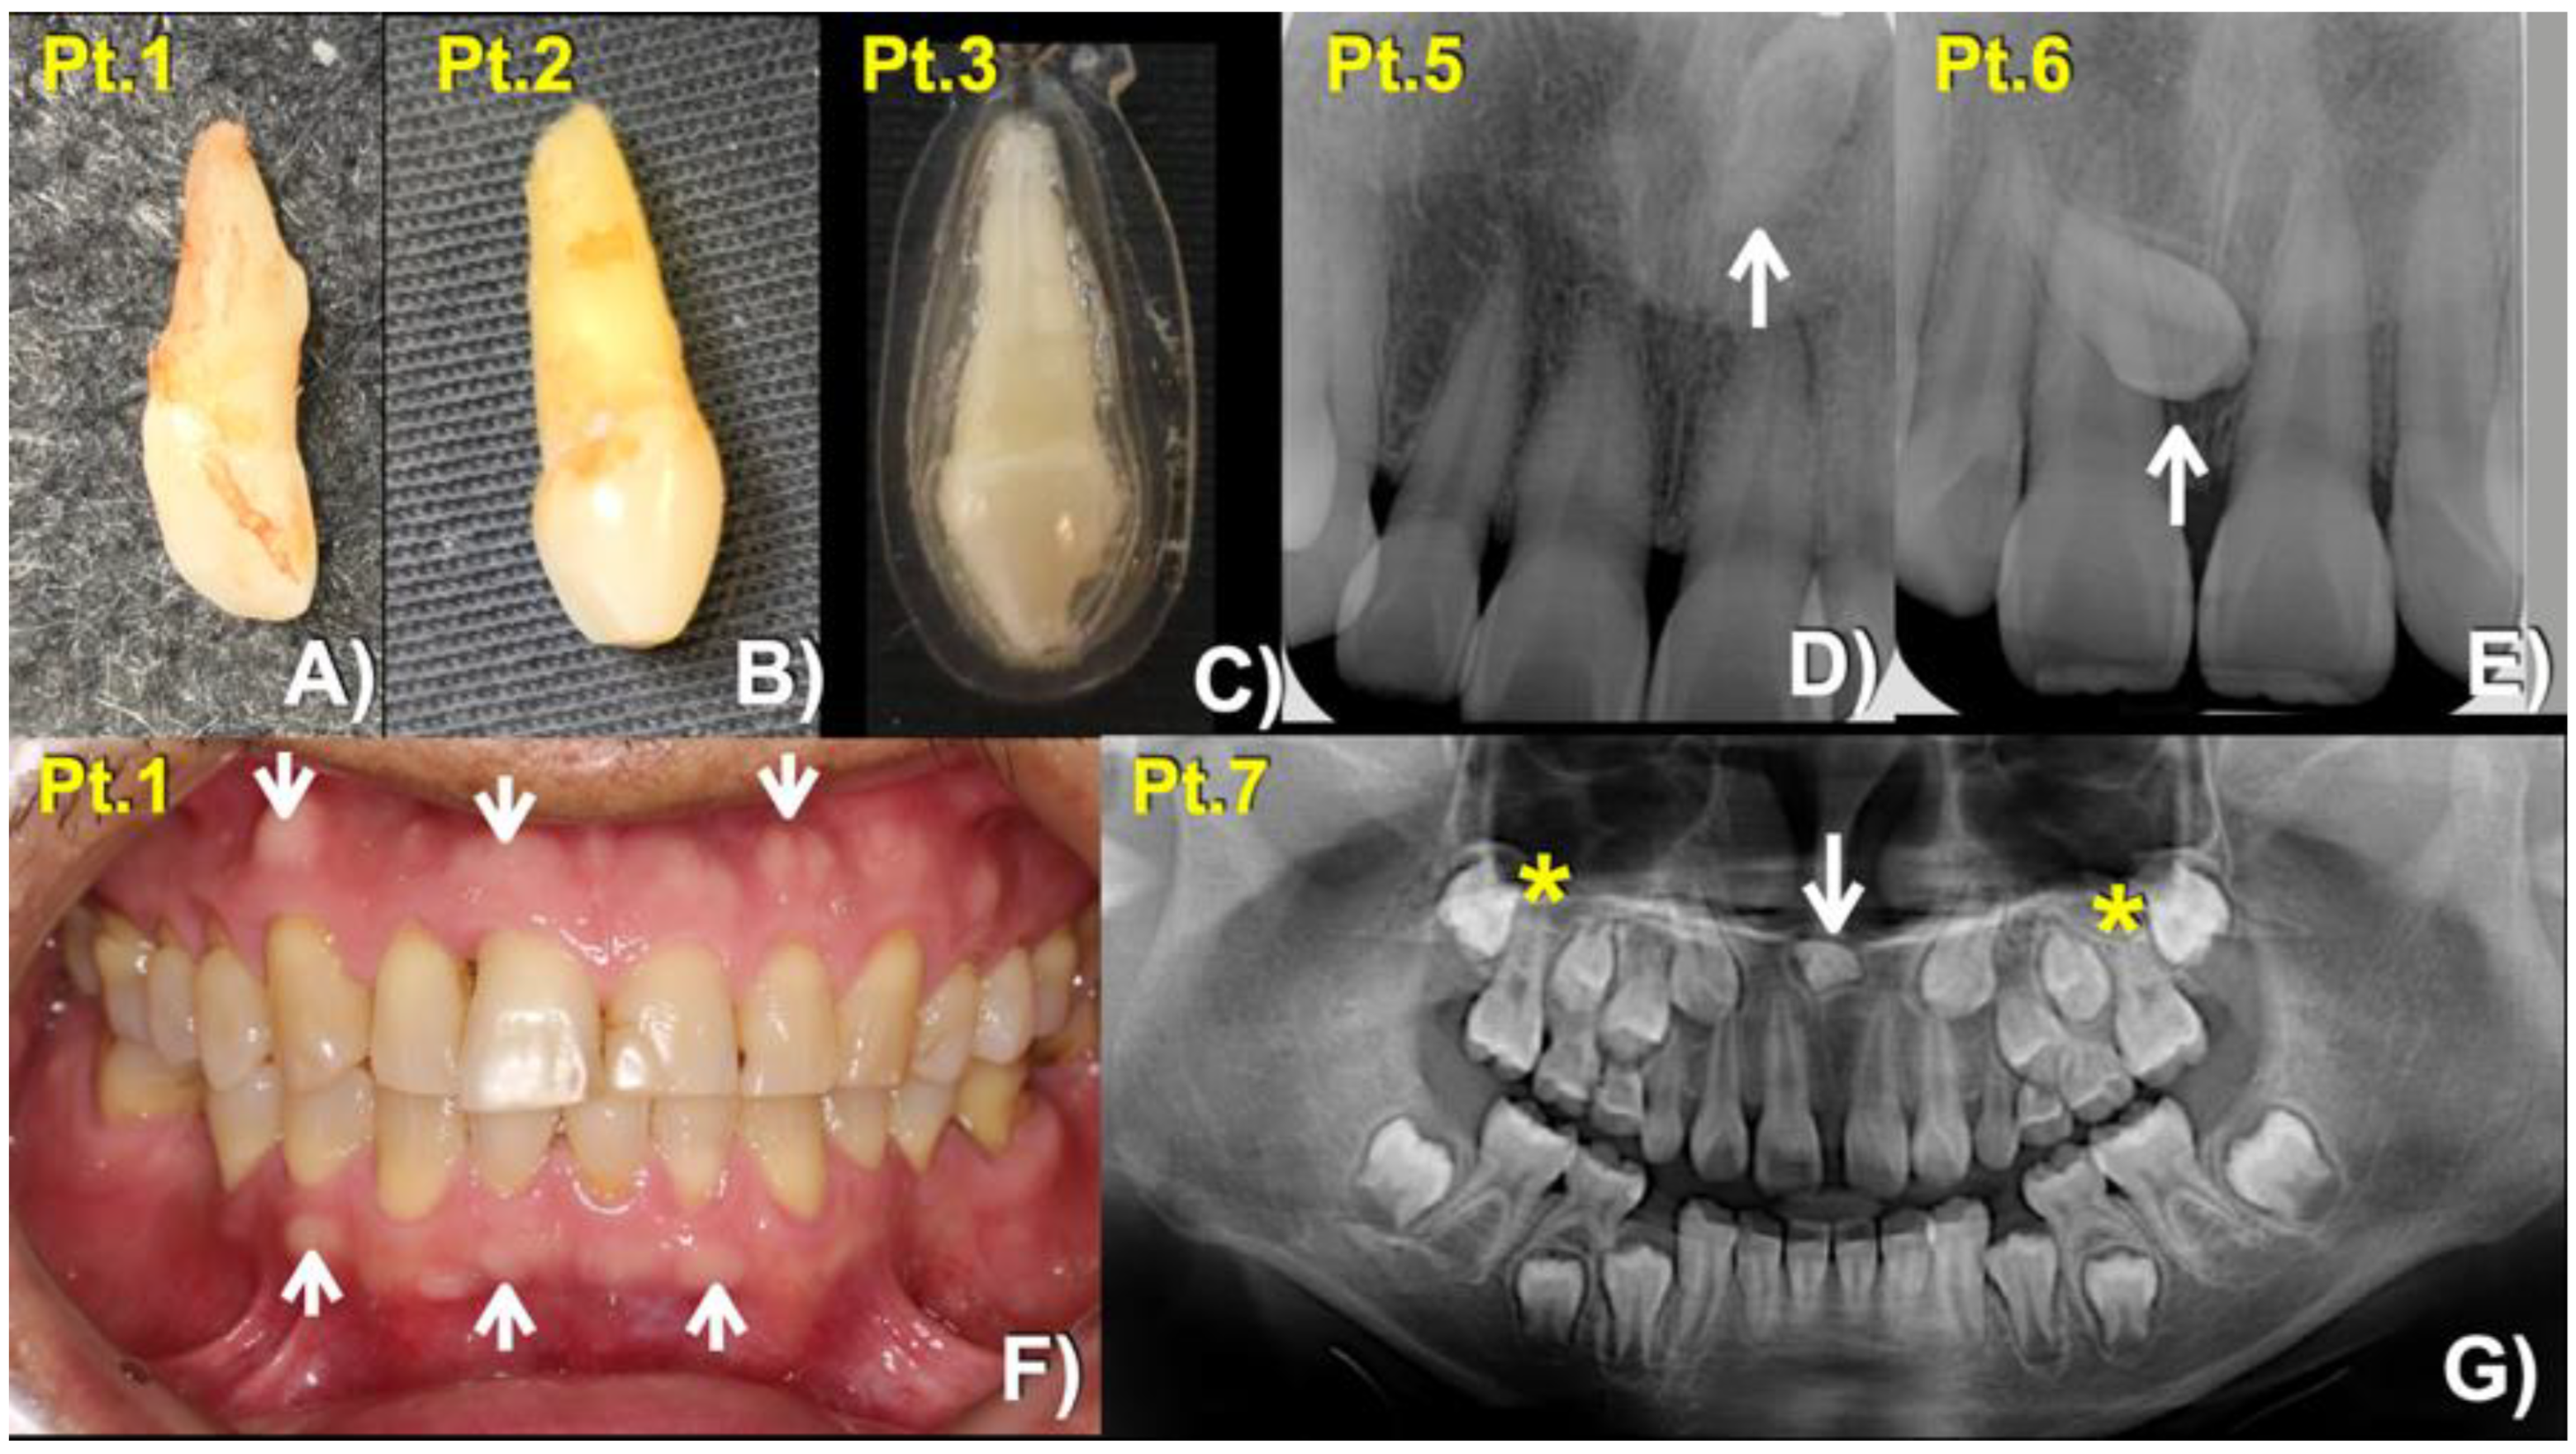

| 1 (Male: 52 Yr) | 1 | Mesiodens (Conical; erupted) buccal exostoses | c.4154A > G; p.Asn1385Ser chr11:g.46896426T > C rs768733310, MAF: 0.00001768 | 0.9926 (pathogenic) | 22.3 |

| 2 (Female: 33 Yr) | Mesiodens (Conical; erupted) | ||||

| 3 (Female: 17 Yr) Homozygous | Mesiodens (Conical; erupted) | ||||

| 4 (Female: 30 Yr) | 2 | Mesiodens (Conical; unerupted) long roots of mandibular canines, short roots of second premolars, unseparated roots of second and third molars, torus mandibularis, and torus palatinus | c.3940G > A; p.Gly1314Ser chr11: g.46896640 C > T rs371961330 MAF = 0.00009579 | 0.9966 (pathogenic) | 18.11 |

| 5 (Female: 41 Yr) | 3 | Mesiodens (Inverted; unerupted) | |||

| 6 (Male: 13 Yr) | Mesiodens (Unerupted, tuberculate) | ||||

| 7 (Female: 9 Yr) | 4 | Mesiodens (inverted; unerupted) unseparated roots of the maxillary first molars | c.448G > A; p.Asp150Asn chr11:g.46921037C > T rs200746048, MAF: 0.00002787 | 0.9925 (pathogenic) | 22.3 |